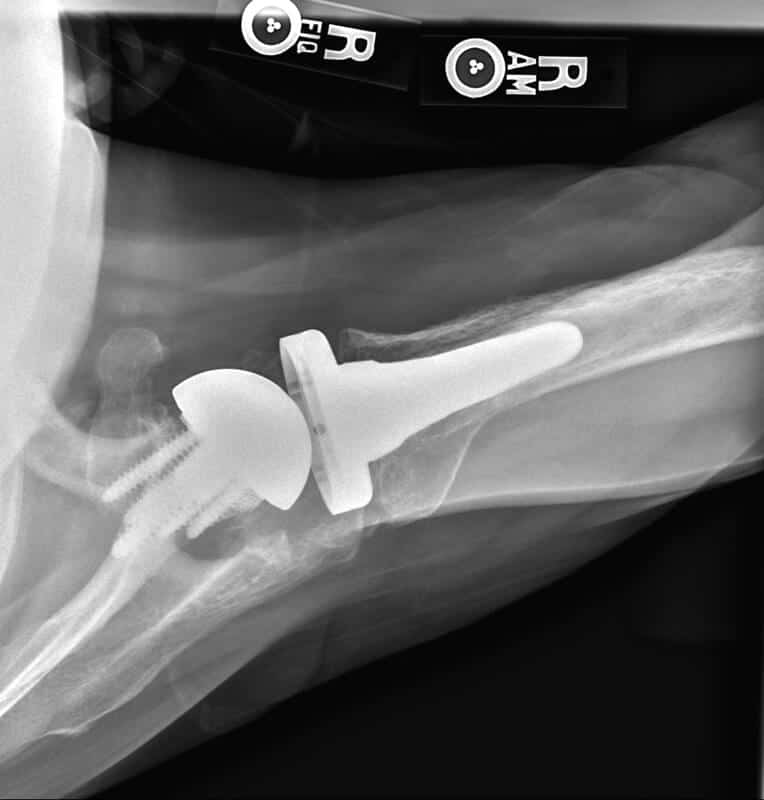

Stryker/Wright/Tornier, Flex Ascend Humerus, Perform Half Wedge Glenoid